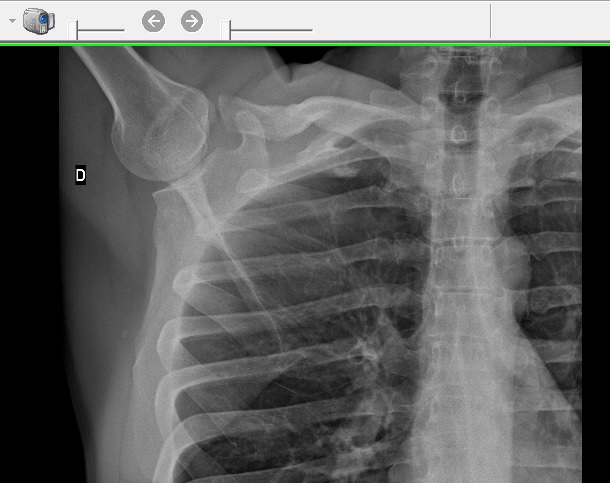

Ieri, dopo l’allenamento, mi è venuto un torcicollo micidiale. Non SUBITO dopo in realtà, diciamo 4 o 5 ore dopo a dire il vero, e durante l’allenamento non ho nemmeno subito traumi di qualche tipo perciò non l’ho nemmeno legato all’allenamento stesso lì per lì e ho solo aspettato che passasse. Dopo un paio d’ore, siccome il fastidio peggiorava diventando dolore, ho preso un antidolorifico a caso che avevo in casa e che non ha fatto alcun effetto. La sera ho preso una tachipirina 1000 e ho dormito bene, salvo poi svegliarmi con lo stesso torcicollo. Mia moglie stamattina mi ha toccato un po e a un certo punto si è resa conto che tra il collo e la spalla, solo dal lato destro, ho una specie di piccola protuberanza ossea che dall’altro lato non c’è. Cioè, non è che esca un osso eh! Diciamo più che altro un ossicino. Si vede appena appena ad occhio nudo e però al tatto è evidente. Però mi sembra strano…. Fosse un osso che è uscito da dove deve stare , starei morendo dal dolore, no? Voglio dire: non avrei un torcicollo ma starei proprio morendo dal dolore. Questa considerazione è l’unica cosa che mi consola. Allo stesso tempo mi preoccupa il fatto che comunque quest’ossicino è lì e dall’altra parte non c’è. E non è una cosa che sto immaginando (sarebbe pure possibile dato che sono un pochetto ipocondriaco) ma è mia moglie che se n’è accorta per prima. E comunque questa cosa non mi sembra normale, tantomeno legata a un forte torcicollo improvviso. Fosse solo torcicollo mi riposerei e aspetterei, così invece è un po’ diverso. Vabbè, comunque oggi sicuramente mi riposo lo stesso. Intanto sento la mia dottoressa di base che mi darà appuntamento tra 2 settimane che quando mi capita di avere un qualsiasi tipo di problema, dal momento che chiamo al momento che mi riceve, di solito ho dimenticato per cosa andavo là ahahah… ma vabbè questo è un altro discorso… ….al Pronto Soccorso invece non ci voglio andare perché, se non stai morendo, vuol dire passare lì 5 o 6 ore come niente e proprio non c’ho palle e tempo di far sta cosa…..